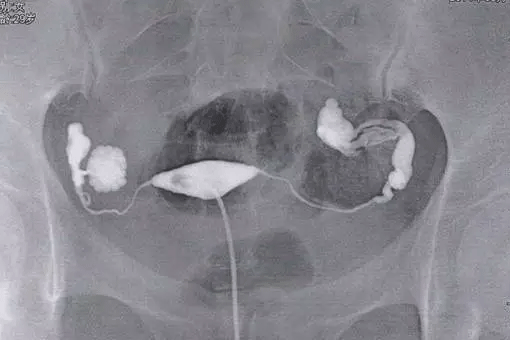

子宫输卵管造影是判断输卵管疏通与否的一种检查方法,包括输卵管造影在内,关于输卵管检查的几种类型还有输卵管通液、超声检查、腹腔镜检查、输卵管通气试验等,以上这些都是针对女性输卵管是否正常的一些检查方法。

整个输卵管造影流程下来,对女性身体的伤害较小,同时在有经验的医验操作下准确率高达98%,输卵管造影相比宫腔镜、腹腔镜、输卵管镜等检查来说,在许多方面是无法替代的,下面来看看详细的输卵管造影过程:

①、在进行输卵管造影检查时,首先患者需要仰卧在X光机操作平台上,先常规消毒外阴及阴道,同时铺无菌巾,再次检查子宫位置及大小;

②、随后在医生会用窥器扩张阴道,暴露宫颈,消毒完毕后再将宫颈管顺着宫腔的方向插入,然后在拉紧子宫颈钳使导管之锥形橡皮头与宫颈紧紧相贴,以防止药物的流出;

③、然后只需要在X线透视下观察造影剂流经宫腔,再慢慢注入碘油,观察子宫及流经输卵管的情况,此时会拍摄一张照片然后会继续推入碘油,5--10分钟后继续拍片;

④、间隔一天时间后会在同部位拍摄,如果双侧输卵管不通那么久不会有游离的碘海醇,如果有少量碘海醇那么确定为输卵管通而不畅。